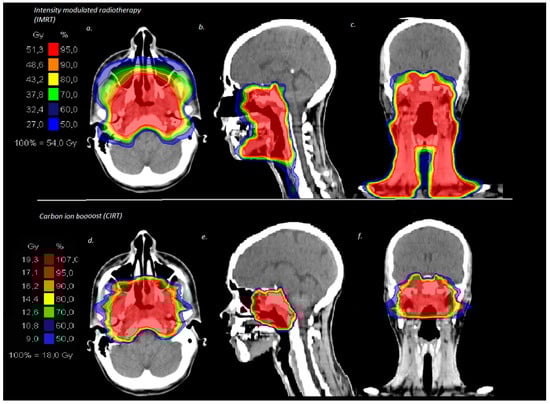

| 50 Gy/2 Gy IMRT + 24 Gy/3 Gy (RBE) C12 | 5 (19) |

| 56 Gy/2 Gy IMRT + 18 Gy/3 Gy (RBE) C12 | 21 (81) |

| median total dose | 74 Gy (RBE) (72–74 Gy (RBE)) |